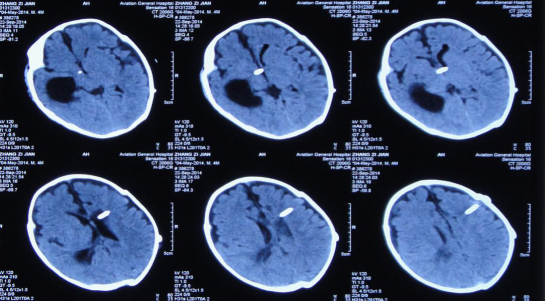

入院当天行脑室外引流术,引流的脑脊液淡黄色,细菌培养为无细菌,经引流第34天查头CT时,发现:右侧颞角孤立性扩大,其余脑室系统明显缩小。

治疗第42天行右侧侧脑室颞角引流术,第47天复查头CT: 右侧颞角及其余脑室系统大小正常,第63天行双侧脑室分流术,第74天出院,头围减小至39cm(活泼好动,恢复正常。